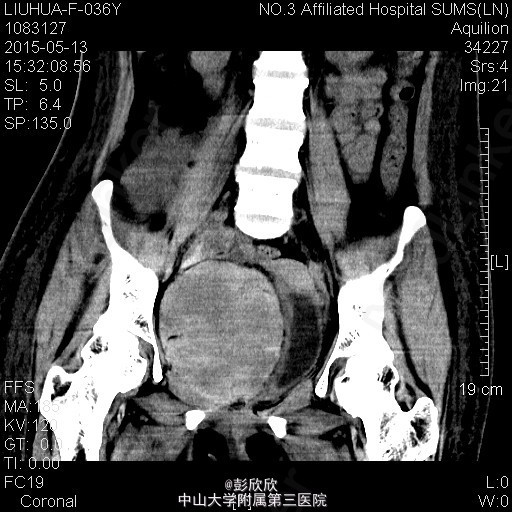

患者女,36岁,因尿毒症与2015-5-9在我院行异体肾移植术,手术过程顺利,术后恢复良好,术后第5天出现移植肾周胀痛不适、头晕、右下肢水肿,检测血常规发现血色素明显降低,考虑体内存在出血,行紧急CT检查提示移植肾下极有一个巨大血肿,考虑有活动性出血,给予输血、使用止血药物等保守治疗措施。

患者右下肢肿胀,移植肾周压痛明显,面色稍苍白。行紧急腹部CT检查提示移植肾下极巨大血肿

诊断:移植肾周巨大血肿,活动性出血? 处理:给予患者紧急输血、补液和药物止血,动态监测血红蛋白,确定没有活动性出血后在彩超引导性行移植肾周穿刺引流术,引出陈旧性积血约600ml。之后密切监测患者生命体征,继续输液、免疫抑制等对症治疗。